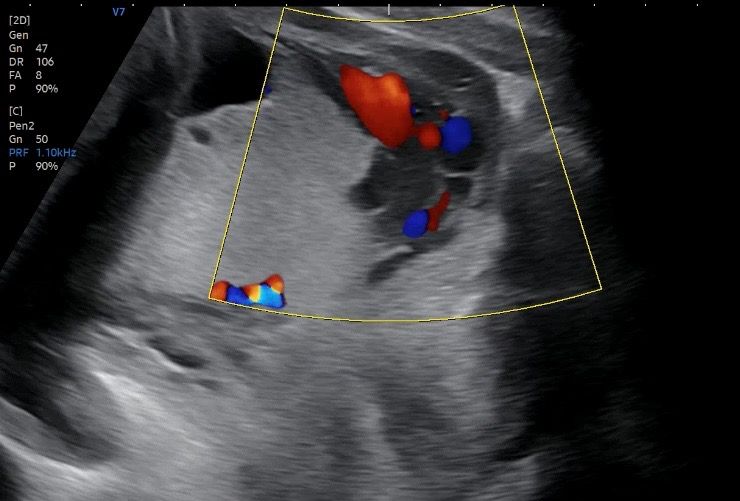

• 1번 째 사진

• 26주에 완전 전치태반(complete placenta previa) 이 진단된 경우, 이후 자궁 성장에 따라 태반이 자궁경부 내구에서 벗어날 가능성은 있지만 높지는 않습니다.

임신 중기(20주 전후)에 진단된 전치태반의 상당수는 자궁 하부가 늘어나면서 상대적으로 “올라가 보이는” 현상이 나타날 수 있습니다. 그러나 26주 시점의 ‘완전’ 전치태반은 단순 변연성이나 저위 태반과는 다릅니다. 여러 관찰 연구에서 24주에서 28주 이후까지 지속되는 완전 전치태반이 30주 이전에 정상 위치로 이동할 확률은 대략 5에서 15퍼센트 정도로 보고됩니다. 32주 이후까지 지속되면 자연 소실 가능성은 더 낮아집니다.

초음파에서 태반이 자궁경부를 완전히 덮고 있고, 태반의 중심부가 내구에 걸쳐 있는 경우일수록 이동 가능성은 낮습니다. 또한 이전 제왕절개 병력, 태반이 후벽이 아닌 전벽에 위치한 경우, 태반 면적이 큰 경우에도 호전 가능성은 줄어듭니다.